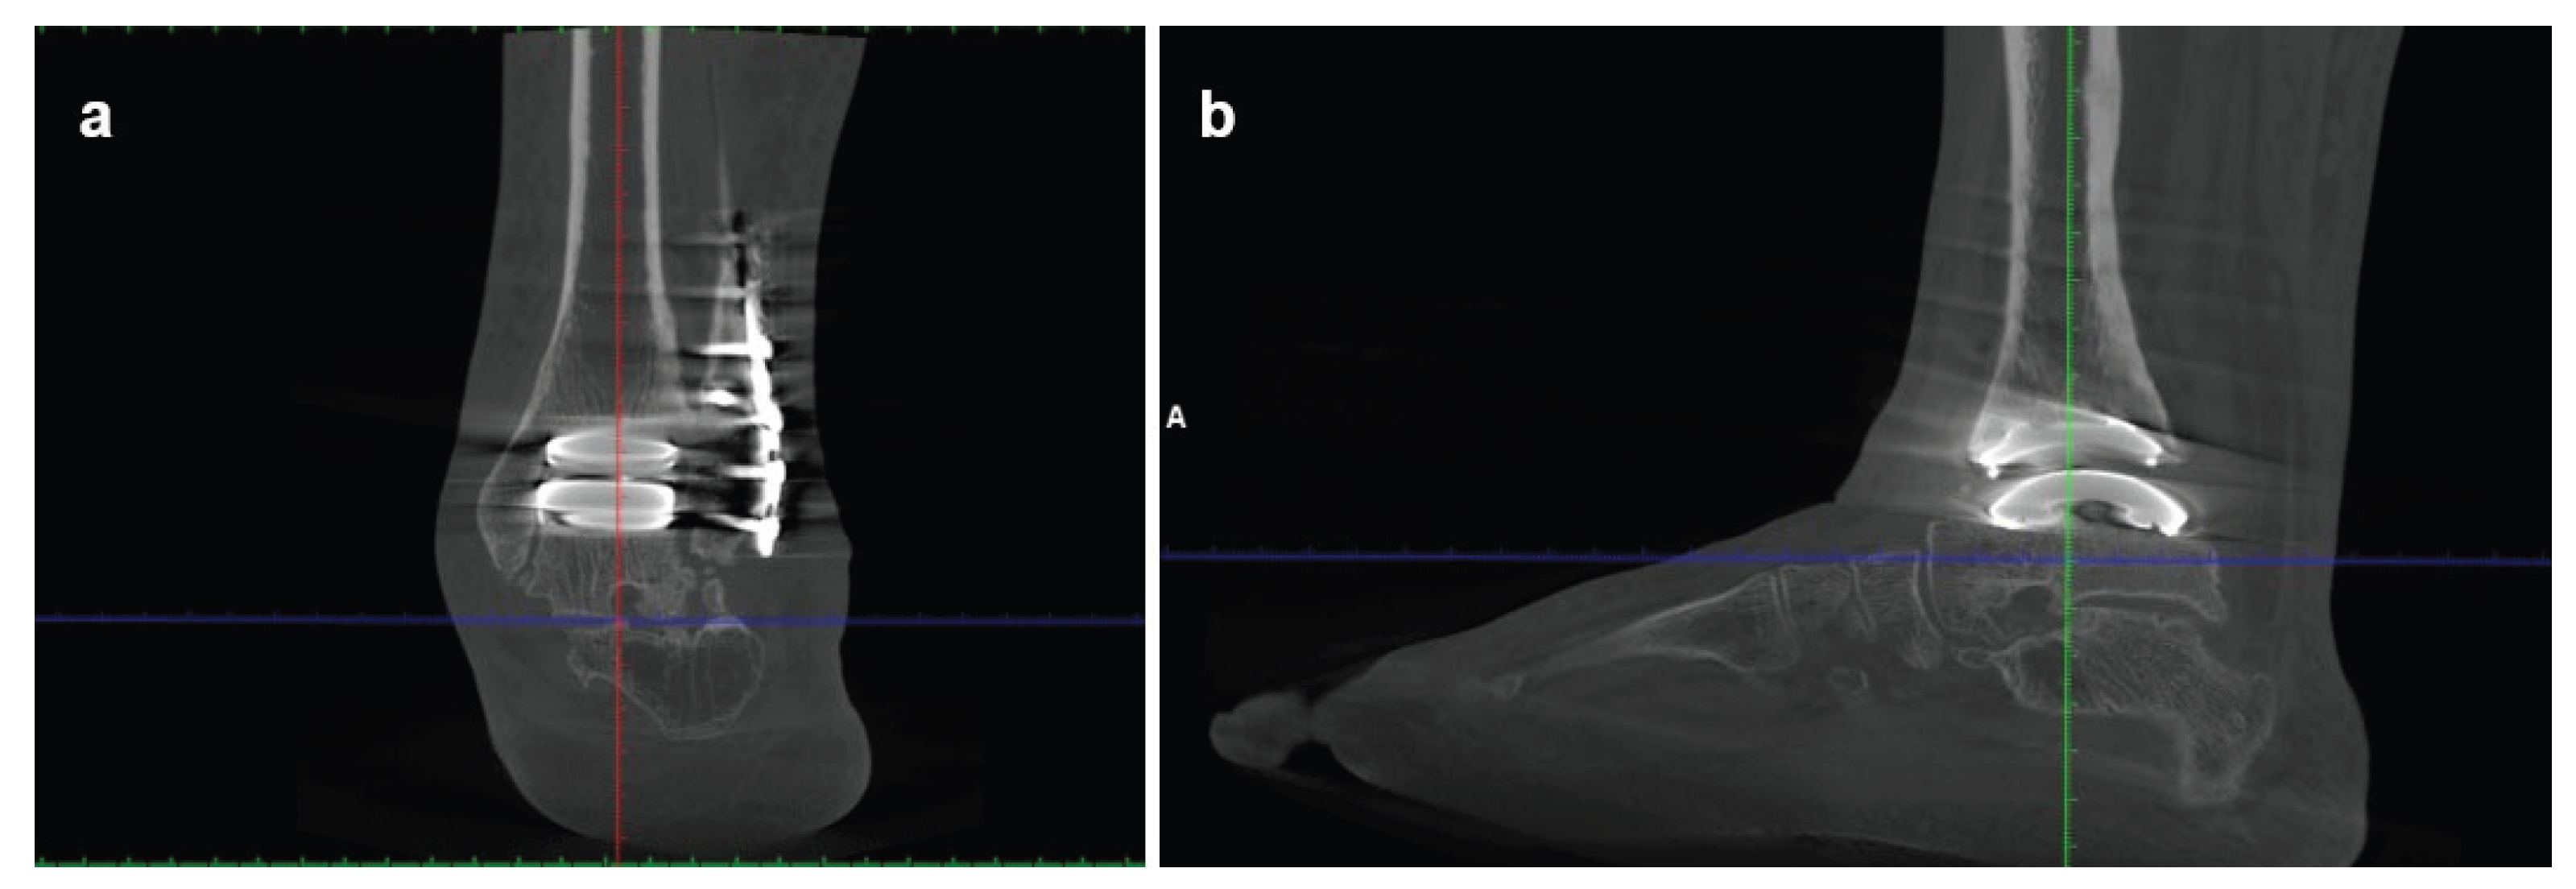

Imaging, including bilateral weight-bearing X-rays (Figure 4) and WBCT (Figure 5), demonstrated end-stage tibiotalar osteoarthritis (Kellgren–Lawrence grade 4[8]) with distal tibial and distal fibular bone deformity. The ankle showed a valgus alignment with posterior shift of the talus. Early degenerative changes were also observed in the talonavicular and subtalar joints. The midshaft of the fibula displayed residual deformity from previous surgical procedures. Radiographic measurements are summarized in Table 2. The patient gave informed consent for the publication of his clinical details and images.

The patient was reviewed at 6, 12, 24 and 36 months postoperatively. Clinically, he demonstrated progressive improvement in gait pattern, consistent with his previous knee fusion, and ankle range of motion, achieving a painless 10° dorsiflexion and 30° plantarflexion (VAS 0). Imaging at each follow-up showed a stable implant with correct alignment and no evidence of subsidence (Figure 6). Post-operative radiographic measurements are summarized in Table 2. By the last follow-up, he had returned to his normal daily activities and remained pain-free. The patient gave informed consent for the publication of his clinical details and images.

Figure 5. Preoperative weight-bearing computed tomography (WBCT) scans of Case two: (a) coronal and (b) sagittal views showing severe tibiotalar osteoarthritis with valgus malalignment, distal tibial and fibular deformities, posterior talar displacement.

Figure 6. Postoperative coronal (a) and sagittal (b) WBCT views at 3-year follow-up of Case two, demonstrating accurate implant positioning with restoration of alignment, and preservation of implant stability and bone integration without signs of loosening.